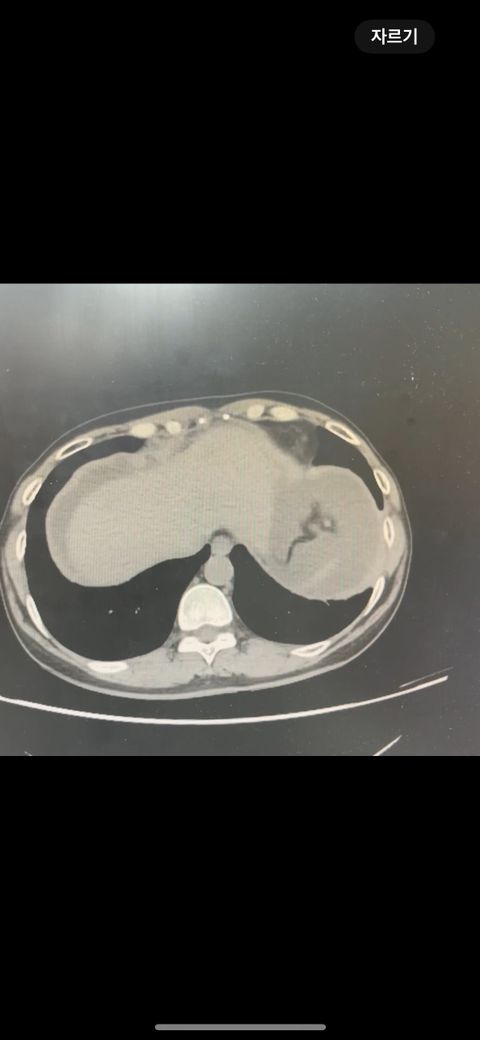

복부 ct 판독 부탁드립니다 (contrast)

결과는 3일 뒤 보긴 하는데 우선 영상만 있는 상태라 영상 캡쳐 한 거 대략적으로라도 확인해주실 수 있나요.. !!!!!!!!!!

• 1번 째 사진

*** 먼저 답변드리기에 앞서 상기 질문에 대한 답변은 굉장히 제한된 답변이고, 경우에 따라 틀린 답변이 될 수 있습니다. CT의 경우 단면을 연속적으로 봐야 의학적인 설명이 가능하기 때문에 일부 사진만으로는 해석이 어려울 수 있습니다.

위 사진에서는 비장비대의 가능성과 자궁쪽으로 혹이 일부 보이는 소견이 의심되나, 정확한 판독은 3일 뒤에 받아보시는 것이 도움이 될 수 있겠습니다.